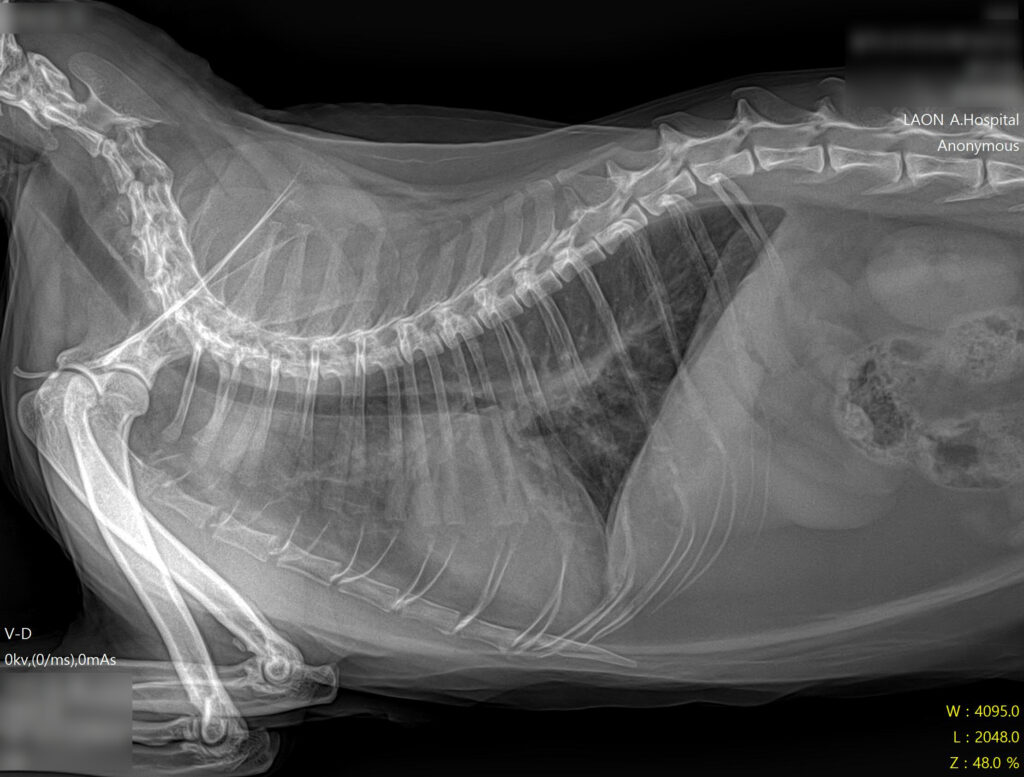

* 폐야가 하얗게 변한 폐수종 소견과 비대해진 심장 확인

- 방사선 검사: 흉부 방사선 촬영 결과, 폐 전반에 걸친 폐부종(pulmonary edema) 소견이 확인되었습니다. 또한 심장의 실루엣이 전형적인 ‘Valentine Shape(발렌타인 하트 모양)’으로 관찰되었는데, 이는 HCM(비대성 심근병증)에서 나타나는 특징적인 방사선 소견입니다.

* 폐수종 개선 및 깨끗해진 폐야 확인